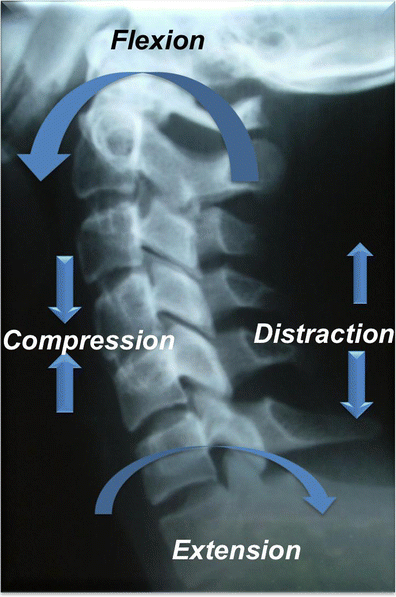

Schematic shows major injury vectors and forces with their impacts on the vertebral column. Flexion injury results from supraphysiological forward bending and extension injury results from backward banding. Compression forces approximate the bones, while distraction dissociates the bones. Shear forces are applied at a right angle to the long axis of spine and produces significant bony and ligamentous disruption